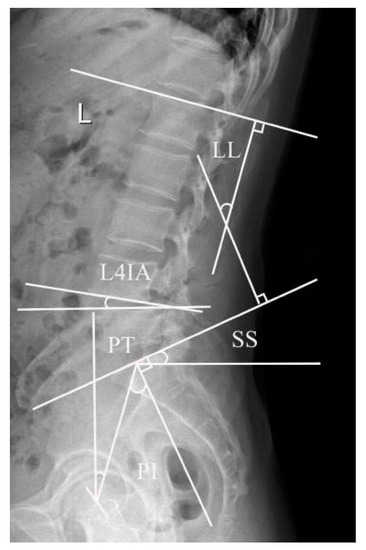

2.4.4. Evaluation of PVM Change

The multifidus muscle (MM) has been the most studied and commonly used measurement with which to evaluate the fat infiltration and atrophy of PVM [11,12]. The percentage of the fat infiltration area (%FIA) was measured via axial T2-weighed imaging at the L4-L5 disc level by using ImageJ software (Version 2.0.0, National Institutes of Health, Bethesda, MD, USA). First, we converted each image into a grayscale 8-bit image. We then outlined the region of the multifidus muscle using the threshold technique and utilized a “default” and “dark background” method to obtain the value of the threshold automatically. Last, we calculated the %FIA; the red area in the 8-bit image was the fat tissue, and the fat tissue divided by the region of the multifidus muscle was the %FIA (Figure 4) [13].

Figure 4.

Example of fat tissue (red color) of the MM showed in the ImageJ software (Version 2.0.0, National Institutes of Health, Bethesda, MD, USA).